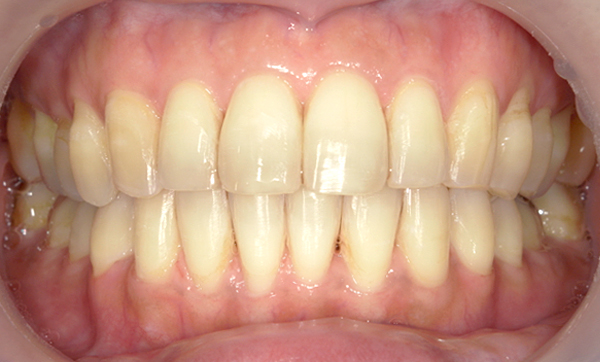

症例_003 前歯「八の字/V字型」症例

治療期間:8ヶ月金額:30万円+税30代女性八の字/V字型上の前歯だけ

| Before | After |